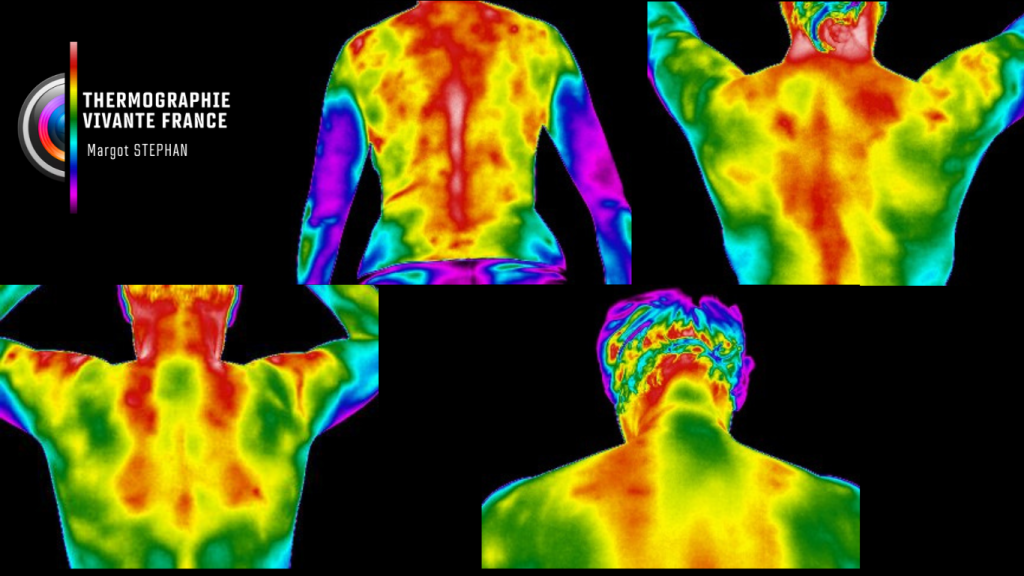

La thermographie vivante est une méthode d’imagerie fonctionnelle non invasive, sans contact, sans rayons, indolore, qui permet de visualiser la carte thermique du corps humain. Elle détecte les variations de température cutanée, révélatrices de phénomènes physiologiques internes : inflammation, surcharge fonctionnelle, tension musculaire, déséquilibres vasculaires, métaboliques ou neurologiques.

Elle révèle plutôt comment ces tissus fonctionnent en temps réel, en mesurant les émissions naturelles de chaleur générées par l’activité métabolique du corps.

La température cutanée que la caméra thermique capte n’est pas un simple reflet de la peau. Elle exprime les interactions profondes entre les systèmes vasculaire, neuromusculaire, inflammatoire et endocrinien.

Elle permet ainsi de détecter :

- Des zones de surchauffe (inflammation, surcharge fonctionnelle)

- Des zones de froid anormal (hypoactivité, trouble circulatoire, déconnexion neurovasculaire)

- Des asymétries thermiques révélant une compensation posturale ou une perturbation fonctionnelle

Sauf cas particulier (ex. thermographie mammaire), chaque premier rendez-vous commence par une cartographie corps entier. Car le corps fonctionne en interactions, pas en pièces détachées.

Une douleur dans l’épaule ? Elle peut être influencée par une surcharge du bassin.

Un déséquilibre thermique au mollet ? Parfois lié à un trouble postural dentaire.

C’est cette lecture systémique, intelligente et comparative qui fait toute la richesse de la thermographie vivante.